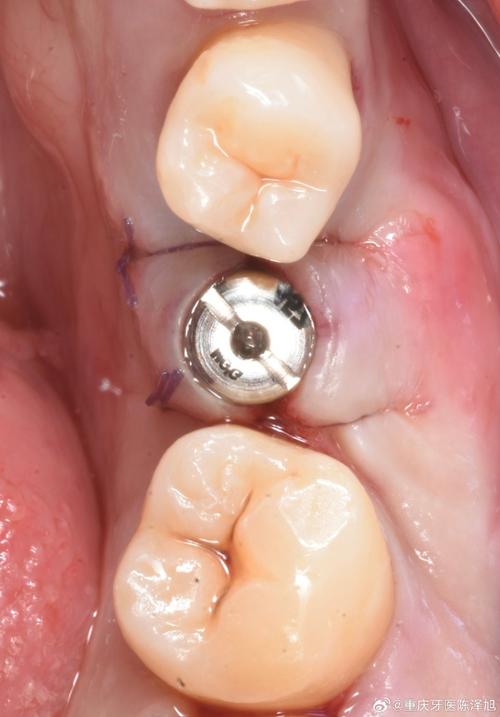

- 安装基台与牙冠:骨结合完成后,通过二次手术切开牙龈,暴露种植体顶部,安装基台(连接种植体与牙冠的中间结构),再取模制作牙冠(全瓷冠、烤瓷冠等),约1-2周后戴牙冠,最终完成的种植牙在外观、色泽、咀嚼功能上均接近天然牙。